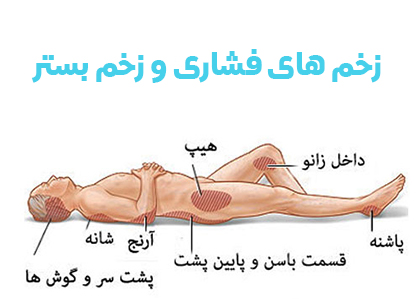

قیمت: 78٬000 تومان - دسته بندی فایل: پاورپوینتپاورپوینت مدیریت زخم های فشاری

فروش ویژه پاور پوینت حرفه ای مدیریت زخم های فشاری با تخفیف استثنایی فقط 92 هزار تومان تعداد اسلاید: 42 اسلاید